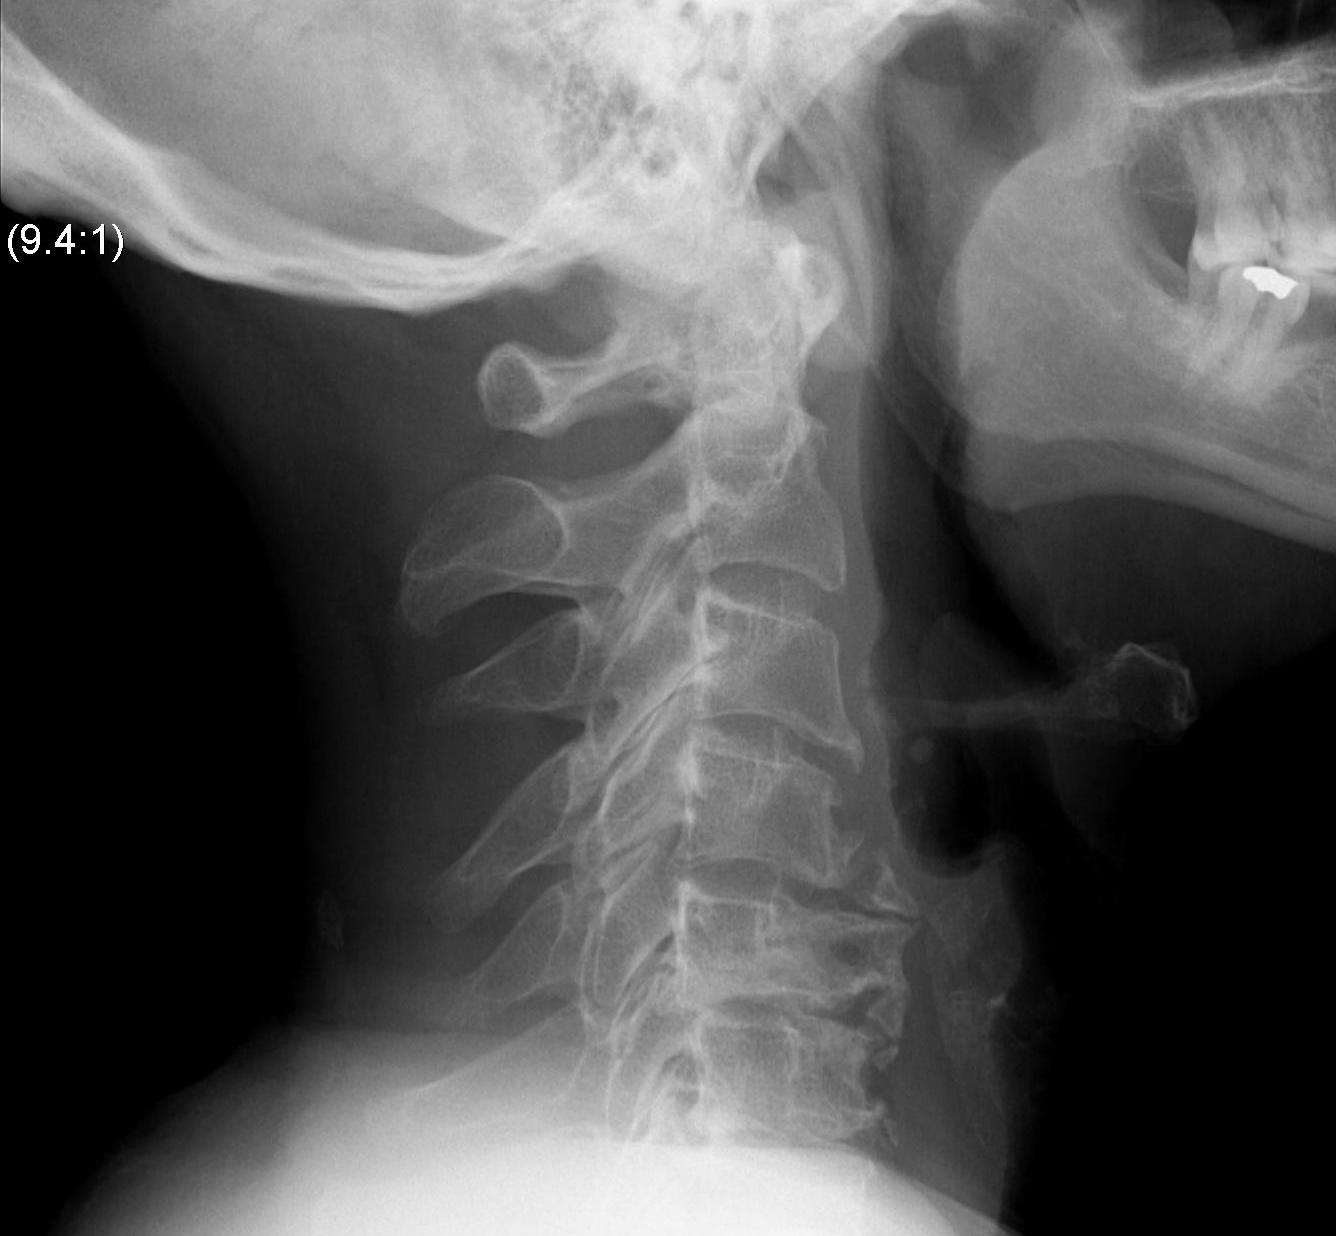

X-ray

Degenerative changes - C5/6 commonest level followed by C6/7

Alignment - lordosis v kyphosis

Ossification PLL

Flexion / Extension views show instability

- > 3 o

- > 11 mm

Torg-Pavlov's Ratio (A/B)

AP diameter of spinal canal (A) divided by the AP diameter of body (B) at same level

- should be 1.0

- < 0.8 is narrowed and stenotic